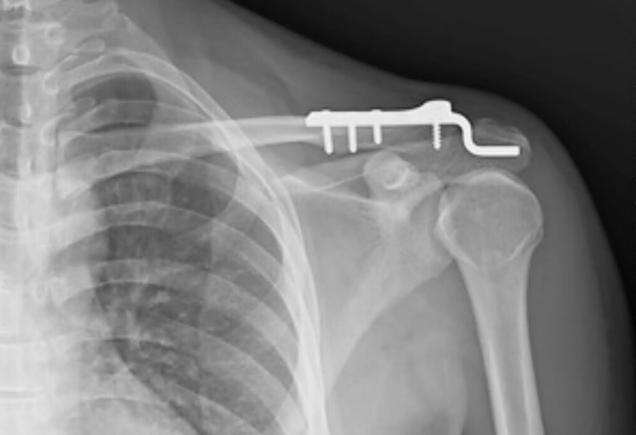

肩周炎是什么病?

肩关节周围炎俗称肩周炎,是以肩关节疼痛和活动受限为主要表现的慢性无菌性炎症性疾病。1、病因机制 肩周炎主要与肩关节囊及周围韧带肌腱退行性变有关。长期过度使用肩关节可能导致肌腱磨损,寒冷刺激可诱发局部血液循环障碍,糖尿病等代谢性疾病患者发病率较高。部分患者发...